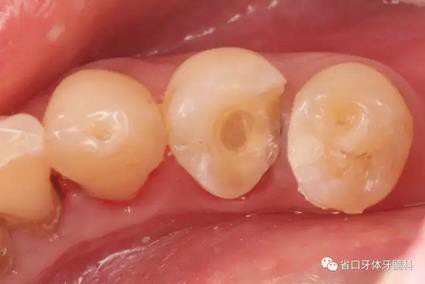

圖4:牙體預(yù)備術(shù)前照

圖5:顯微鏡下34牙體預(yù)備,拋光,35近中樹(shù)脂直接充填,選色偏白